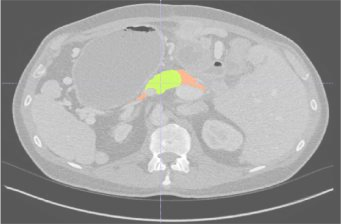

Creating large-scale and well-annotated datasets to train AI algorithms is crucial for automated tumor detection and localization. However, with limited resources, it is challenging to determine the best type of annotations when annotating massive amounts of unlabeled data. To address this issue, we focus on polyps in colonoscopy videos and pancreatic tumors in abdominal CT scans; both applications require significant effort and time for pixel-wise annotation due to the high dimensional nature of the data, involving either temporary or spatial dimensions. In this paper, we develop a new annotation strategy, termed Drag&Drop, which simplifies the annotation process to drag and drop. This annotation strategy is more efficient, particularly for temporal and volumetric imaging, than other types of weak annotations, such as per-pixel, bounding boxes, scribbles, ellipses, and points. Furthermore, to exploit our Drag&Drop annotations, we develop a novel weakly supervised learning method based on the watershed algorithm. Experimental results show that our method achieves better detection and localization performance than alternative weak annotations and, more importantly, achieves similar performance to that trained on detailed per-pixel annotations. Interestingly, we find that, with limited resources, allocating weak annotations from a diverse patient population can foster models more robust to unseen images than allocating per-pixel annotations for a small set of images. In summary, this research proposes an efficient annotation strategy for tumor detection and localization that is less accurate than per-pixel annotations but useful for creating large-scale datasets for screening tumors in various medical modalities.